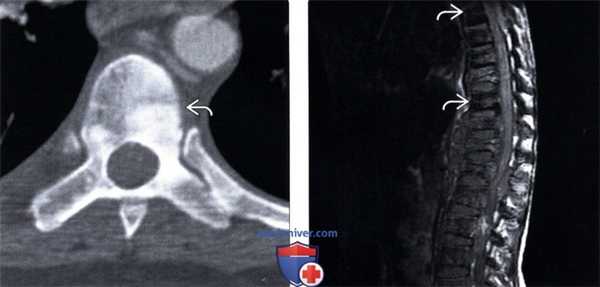

(Слева) Аксиальный КТ-срез: диффузное склерозирование левой половины тела позвонка представляющее собой метастаз у пациента с раком предстательной железы.

(Справа) Сагиттальный срез, Т1-ВИ: диффузное за -мещение костного мозга всех видимых на изображении тел позвонков и множественные компрессионные переломы. При рентгенографии у этого пациента выявлены множественные метастазы саркомы Юинга. Низкая интенсивность сигнала тел Т6 и Т10 позвонков соответствует бластическому характеру метастазов.